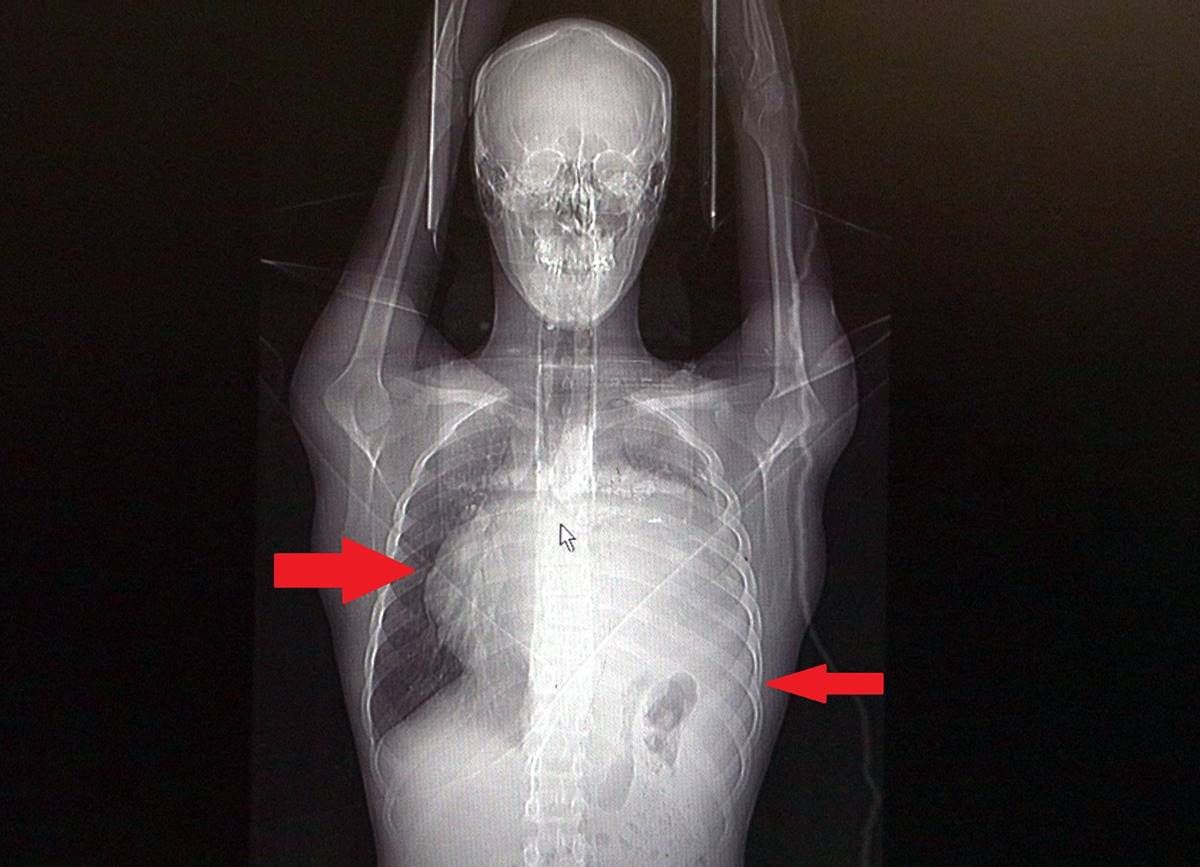

Sol akciğerinin yüzde seksenini kağıt gibi ezen, kalbini göğüs duvarında 12 santim sağa kaydıran ve hem kalbe hem beyne giden ana damarlara baskı yapan 6.5 kilo ağırlığındaki dev tümör, Koşuyolu Yüksek İhtisas Eğitim ve Araştırma Hastanesi Göğüs ve Kalp Damar Cerrahisi ekiplerinin birlikte girdiği operasyonla başarılı şekilde çıkarıldı.

Operasyon sırasında Burak Aktaş'ın kalbi normal yerine çekildi, sol akciğerin üst lobu alındı, ezilen alt lobu ise anestezi ekipleri tarafından pozitif basınçla yeniden şişirildi. Ameliyatı gerçekleştiren ekipten Prof. Dr. Erdal Taşçı, Aktaş’ın göğüs boşluğunun neredeyse tamamını kaplayan 6,5 kiloluk tümörün teratom (eski Yunancada 'canavar tümör') türlerinden biri olduğunu ve embriyonik hücrelerden kaynaklandığını kaydetti.

Sol akciğer tamamen ezilmiş ve kağıt haldeydi, alt lobu anestezi ekibimiz yüksek basınç uygulayarak tekrar şişirdi. Çok fazla vaktimiz yoktu, kitle basısından dolayı yaşamla bağdaşmayacağından dolayı hızlı hareket etmek zorundaydık. Bize geldikten üç gün sonra hemen ameliyata aldık çünkü tümörden ziyade onun yaptığı baskıdan kaynaklı hayati riski vardı."

"Ama bu hastada yaklaşık 12-13 s santimlik kalbin alt ucununu yer değiştirmesi ve kalbe giren çıkan bütün damarlar bükülüp kan akımı bozulmuştu. Kalp Damar Cerrahisi ekibi de bizimle beraber ameliyata girdi. Sol akciğerin üst lobu artık geri dönüşümsüz olarak ezildiği için çıkarmak zorunda kaldık.

Kalbi tekrar eski pozisyonuna getirdik. Ameliyat sonrası çok çabuk toparladı. Koşuyolu ailesi olarak böyle büyük bir vakanın altından başarıyla çıktığımız için de ayrıca çok gururluyuz. Bundan sonra onkolog arkadaşlarımız hastamızın yaşamına çok olumlu dokunuşlar yapacak.